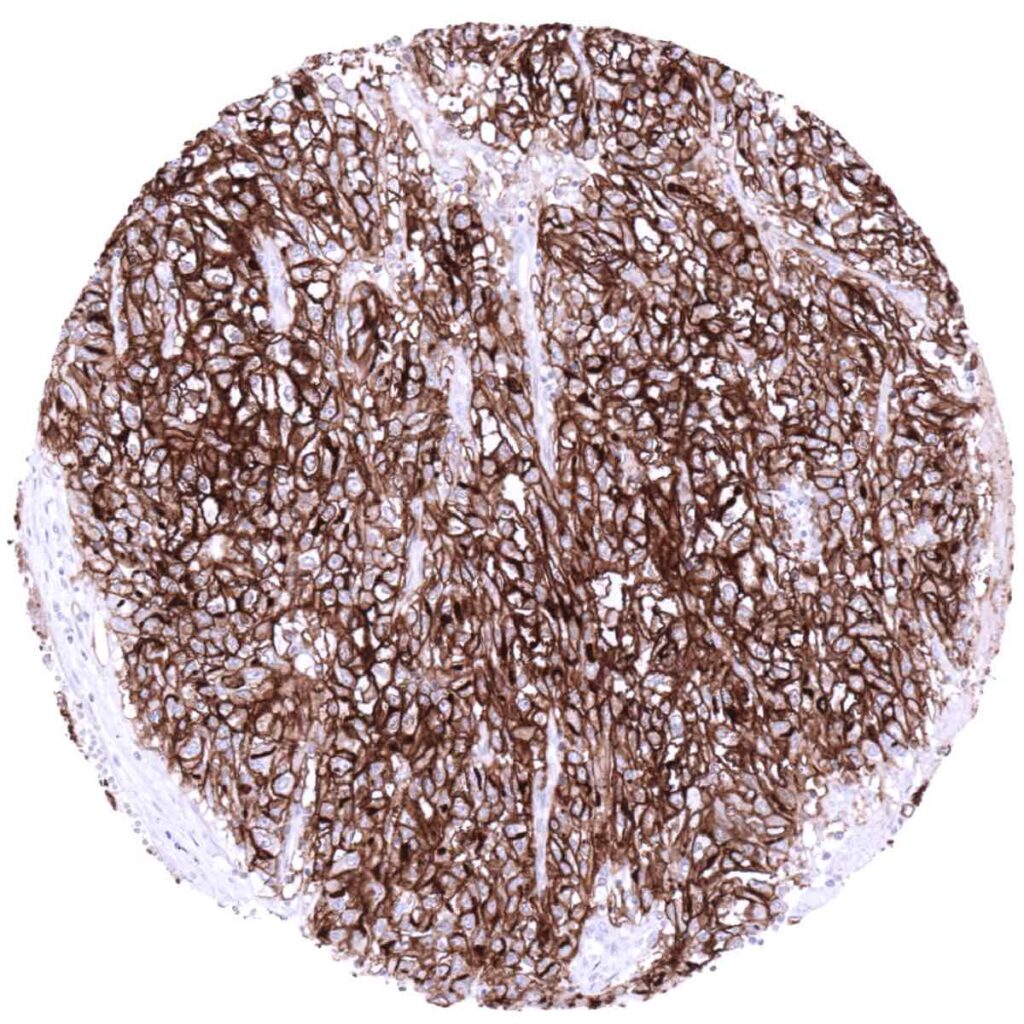

Stomach- Gastric adenocarcinoma (diffuse type) with moderate to strong ACE2 immunostaining of most tumor cells. (ACE2 immunohistochemistry)